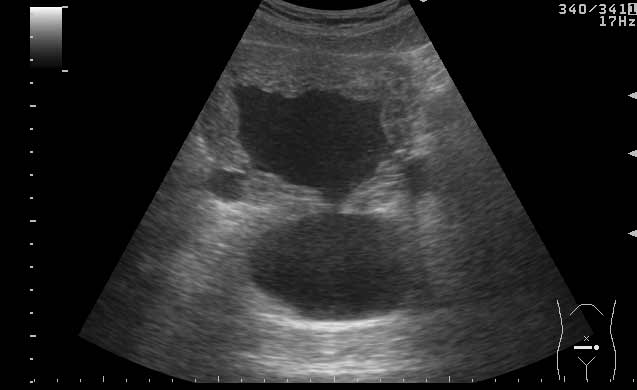

УЗИ мочевого пузыря у пожилого мужчины выявлены следующие изменения.

Signs of chronic urinary retention; evident thickening of the urinary bladder mucosa; large diverticulas. Residual volume evlaluation required; full prostatic assessment is recommended.

But really there are two ones on these pictures.Dr.Mario писал(а):I agree with previous post (Dr. Uzgraph); but there may be much more of them.

неравномерное утолщение стенок мочевого пузыря,признаки застоя в мочевом пузыре,расширенные дистальные отделы мочеточников,на первом снимке-дивертикул?слева,уввеличенная отечная простата

Все верно, за исключением того что простаты на картинках нет. Здорово, что Вы заметили расширение мочеточников. Есть также воздух в МП после цистоскопии.besliu писал(а):неравномерное утолщение стенок мочевого пузыря,признаки застоя в мочевом пузыре,расширенные дистальные отделы мочеточников,на первом снимке-дивертикул?слева,уввеличенная отечная простата